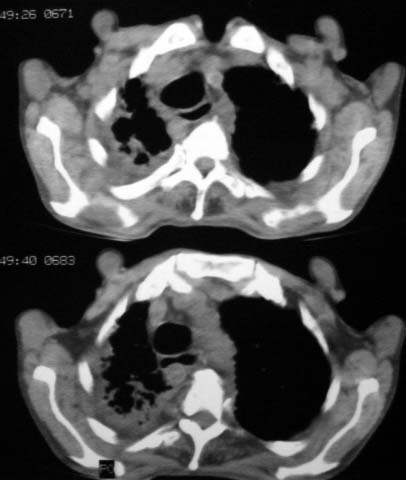

男,85岁,发热2月, 血常规:hgb99g/l.rbc2.55×1012/l.wbc3.8×109/l.n78.2%  l20.7% m1.1%.  hct26.3% .血沉20mm/hg.痰检结核杆菌阴性。ddp阳性。痰少粘稠色白。无咳血。

1.右上肺陈旧性肺结核灶;

右上肺陈旧性肺结核灶,双肺感染灶〔大部份纤维化〕,肺气肿.

双肺继发型肺结核,肺纤维化,肺气肿,胸膜肥厚黏连。